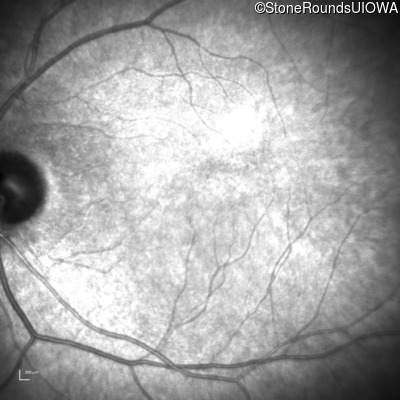

Congenital Stationary Synaptic Dysfunction (IA2g)

Congenital Stationary Synaptic Dysfunction (IA2g)

| Congenital Stationary Synaptic Dysfunction | CABP4 | Arg49Stop CGA>TGA | IVS1+1 G>T | AR |